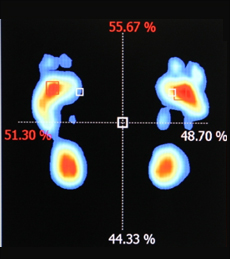

- 족압측정 (골도법)

- 족압을 측정해 발의 기능과 무게중심의

좌우균형을 확인합니다.